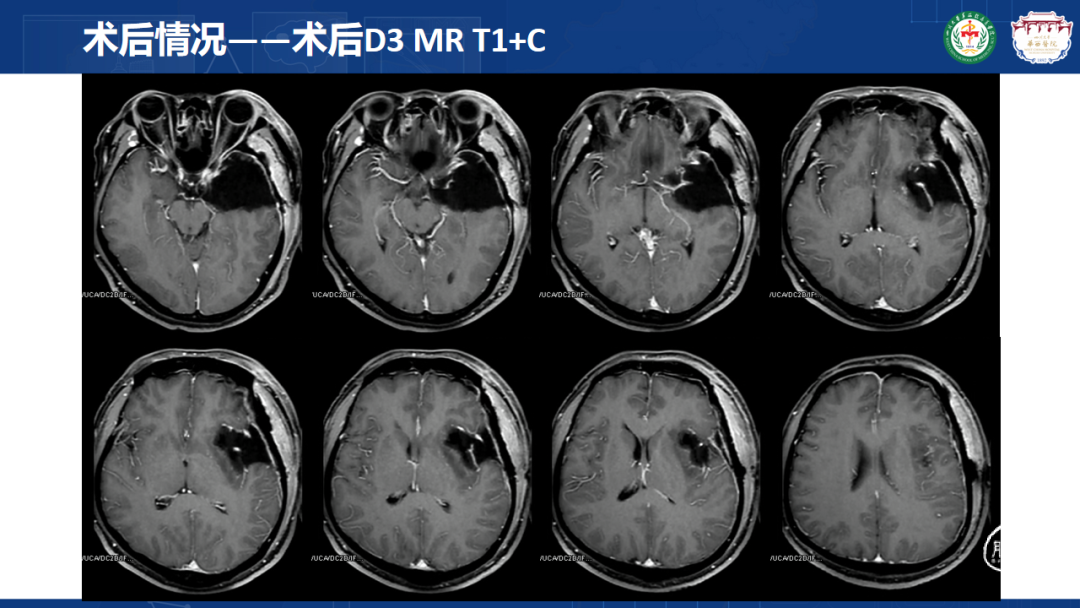

来自四川大学华西医院的曾云辉医师带来《岛叶胶质瘤手术及综合治疗》。该病例是一名41岁男性IT从业者,表现为头晕、右侧肢体麻木伴幻听,MRI显示左侧额颞岛叶占位累及海马头,DTl重建显示肿瘤包绕大脑中动脉分支。术中使用无牵拉技术联合多模态监测,经颞叶皮层造瘘切除病灶,术中重点保护侧裂静脉及M2段穿支血管。术后病理确诊为IDH突变型少突胶质细胞瘤(WHO 3级),规范实施同步放化疗联合6周期替莫唑胺辅助化疗。随访显示肿瘤控制良好,患者神经功能完整并恢复工作。